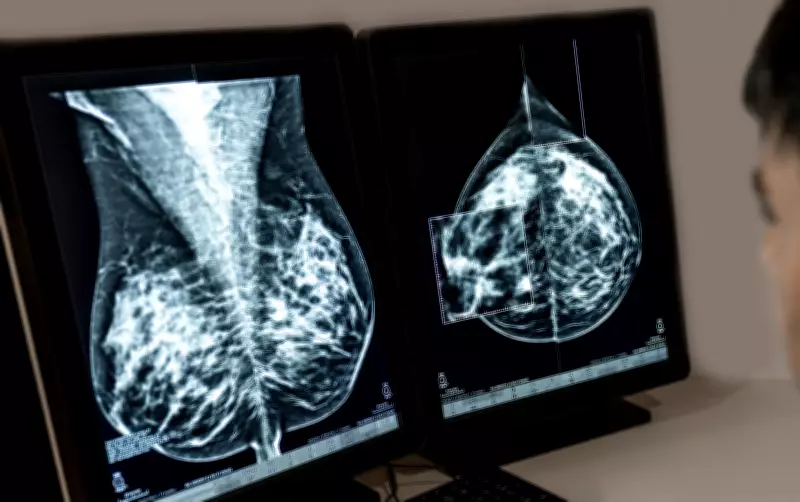

Mama lidera, mas colo do útero segue como alerta grave

Entre as mulheres, o câncer de mama permanece como o mais incidente no país, com números próximos de 80 mil novos casos por ano, tendência semelhante à observada em países desenvolvidos.

“O aumento dos casos de câncer de mama segue uma tendência já vista em muitos países e hoje aparece de forma consolidada, com números próximos de 80 mil novos casos.”